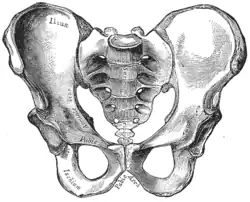

The sacrum and pelvic bone, with parts labelled. The pubic bone consists of the body and superior pubic ramus (4), and the inferior pubic ramus (3), which join at the pubic symphysis. The gap between them is the obturator foramen.

The sacrum and pelvic bone, with parts labelled. The pubic bone consists of the body and superior pubic ramus (4), and the inferior pubic ramus (3), which join at the pubic symphysis. The gap between them is the obturator foramen. Right hip bone. External surface.